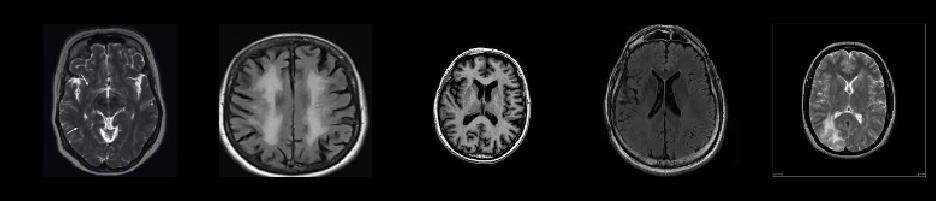

3.1Data Acquisition and Pre-processing: ThefirststepinbuildingthebrainTumorsdetectionmodelinvolvesacquiring a dataset of MRI images containing both Tumors and non-Tumors samples. The notebook may include code snippets for downloading or importing the dataset.[23] Subsequently, the data is pre-processed to ensure consistency and improve model performance. Pre-processing steps may include resizing images, normalization, and augmentation to increase the dataset'sdiversityandrobustness.

3.2Feature Extraction with VGG16: The VGG16 pre-trained model is employed for feature extraction from the MRI images.ThenotebookwouldlikelyincludecodetoloadtheVGG16modelalongwithitsweightstrainedonImageNet.The MRI images are passed through the VGG16 model to extract high-level features. [6] The output features from one of the intermediatelayersofVGG16maybeusedastheinputforthesubsequentclassificationlayer.

3.3Transfer Learning:Transfer learning isutilized toadapt the pre-trained VGG16model to thespecific task of brain Tumors detection. [19] The notebook may include code for fine-tuning the VGG16 model on the brain MRI dataset. This involves freezing the weights of the convolutional layers and training only the newly added classification layers. [9] Additionally, techniques such as learning rate scheduling and early stopping may be implemented to optimize model training.